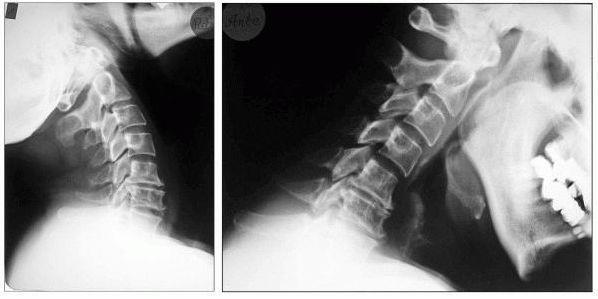

Die Myelograhie dient der speziellen Darstellung des Wirbelkanals im Röntgen-Bild. Dazu wird zunächst durch Lumbalpunktion ein wasserlösliches Kontrastmittel in den Wirbelkanal eingebracht. Die Untersuchung wird bei besonderen Fragestellungen betreffs raumfordernder Prozesse des Spinalkanals, oder bei der Diagnostik ausgeprägter degenerativer Veränderungen im Bereich von Hals- oder Lendenwirbelsäule eingesetzt.

Wörtlich übersetzt: Rückenmarkserkrankung. Meistens tritt sie in Zusammenhang mit einer Rückenkanalsstenose im Halsbereich auf, dann wird sie als cervikale Myelopathie bezeichnet. Sie geht mit Gangstörung (das Gehirn erhält keine Lageempfindungen mehr), Gefühlsstörungen, Lähmungen und Spastik einher.